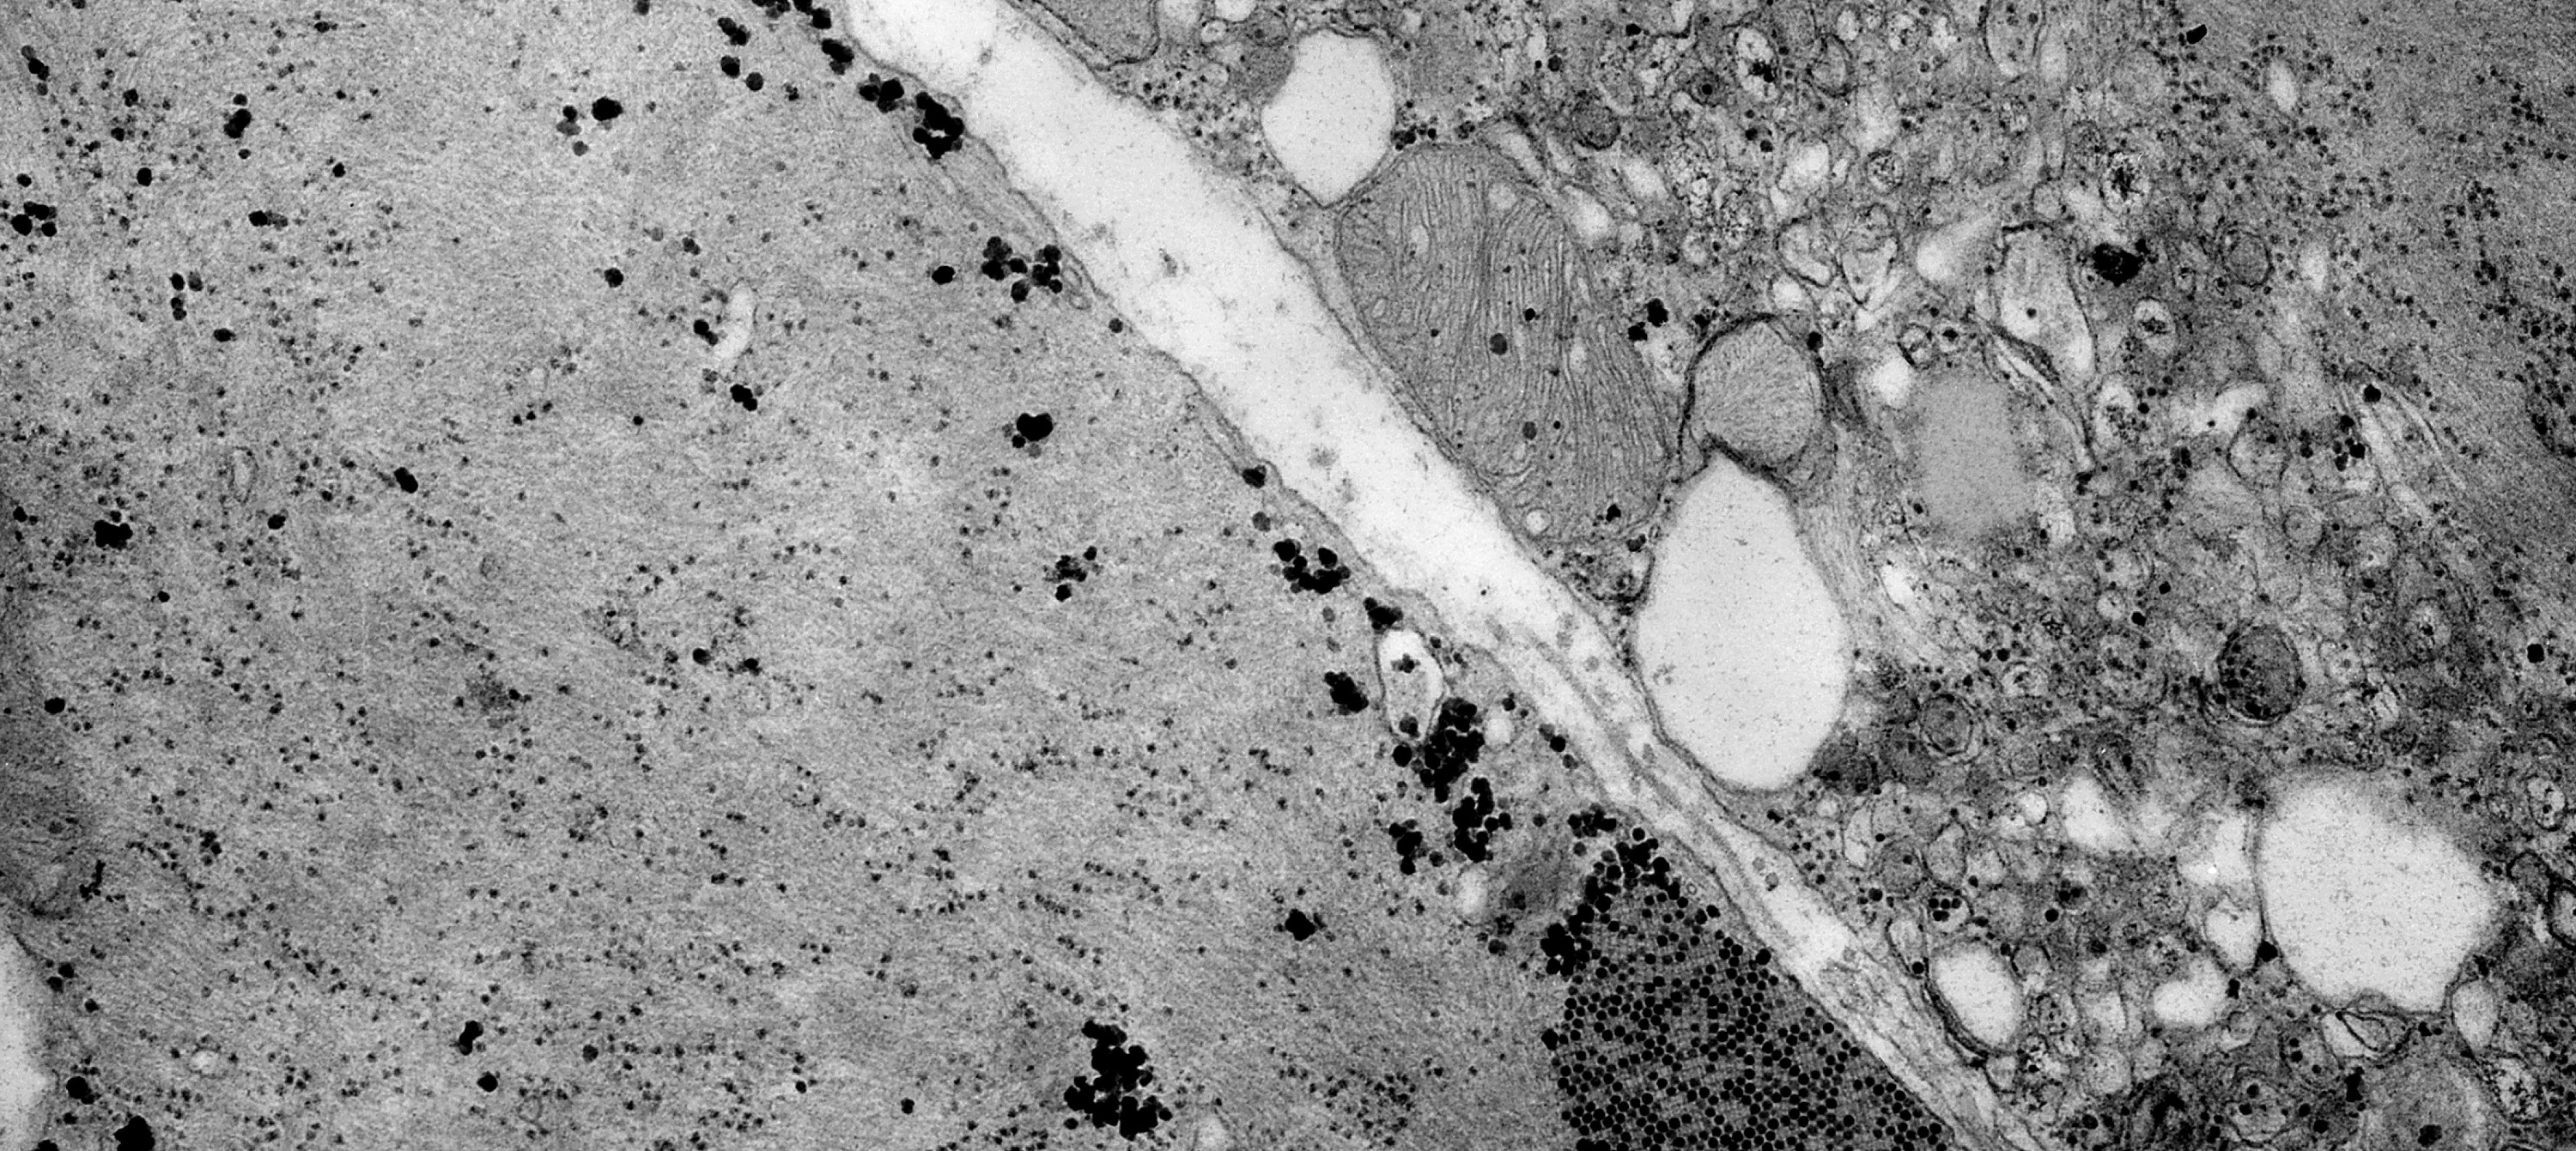

• CIBERER

Un gen asociado a las distrofias de retina regula la función mitocondrial en la retina de los mamíferos

02/06/2021